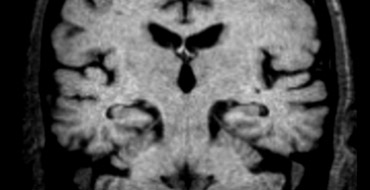

Coronal T1WI of the hippocampus  demonstrating progressive atrophy in familial AD (images kindly provided by Nick Fox). Coronal T1WI of the hippocampus demonstrating progressive atrophy in familial AD (images kindly provided by Nick Fox).

If there is a strong suspicion of Alzheimer's disease, it can be useful to repeat the examination to see if there is any progress of the (medial temporal lobe) atrophy.

The images show a follow-up examination at 18 and 36 months in a patient who was at risk for familial AD, demonstrating progression of the disease.

An alternative approach would be to perform a SPECT- or PET-scan to look for changes in perfusion/metabolism of the temporo-parietal cortex, as these changes precede the development of atrophy.